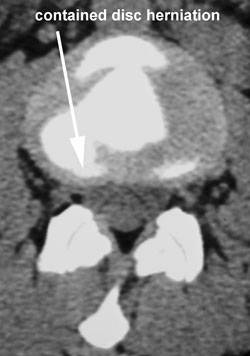

About A Juneau Contained Cervical Spine Disc Herniation

A thorough, clinical examination that may include imaging is important to your recovery.

In-office, Aurora Chiropractic Center uses Cox Technic Flexion Distraction and Decompression to lower the pressure in the disc so the nucleus pulposus returns to the center of the disc, aid in the healing of the torn anular fibers, and drive out chemicals that irritate and inflame the spinal nerves.